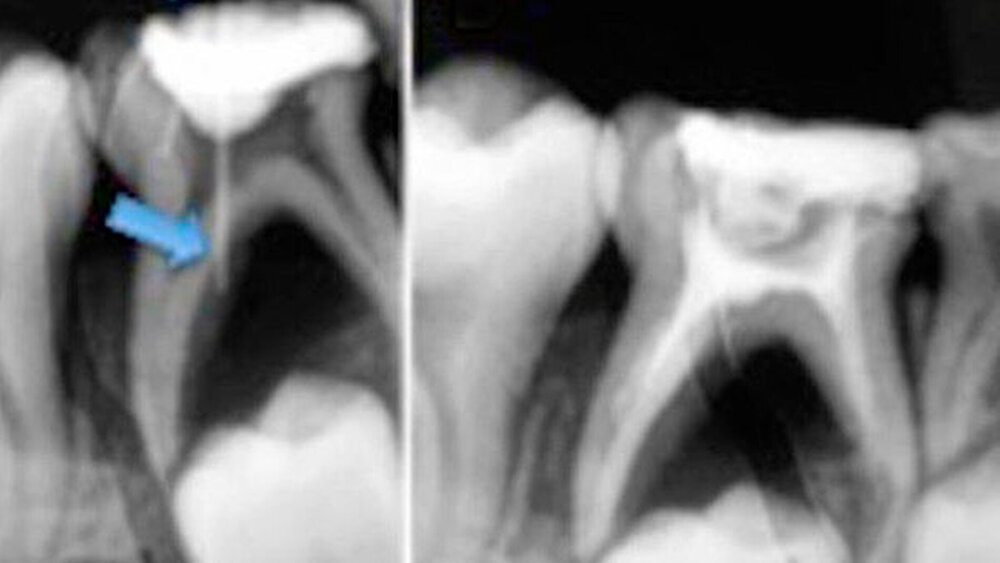

Zunächst wurde ein intraorales periapikales Röntgenbild erstellt, bei dem sich eine diffuse interradikuläre Radioluzenz zeigte, die sich periapikal in Bezug auf Zahn 85 ausdehnte. Der Sinustrakts wurde mit Guttapercha (GP) nachverfolgt: Die Quelle der Läsion wurde unter Verwendung von Röntgenbildern bestimmt und ein entsprechender GP-Punkt festgelegt. Dieser erstreckte sich in den Furkationsbereich von Zahn 85 und bestätigte ihn als Quelle für die Drainage des Sinus.